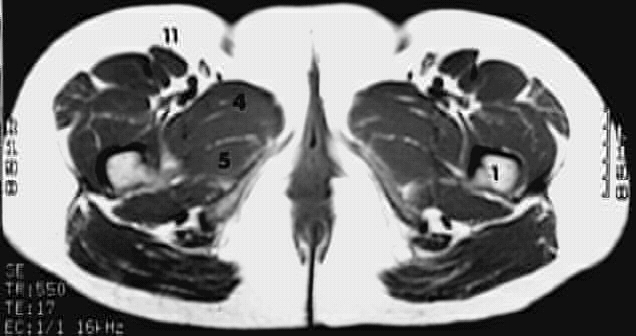

Radiology Images

Lower Limbs: Thigh Cross Zoom 2 of 2